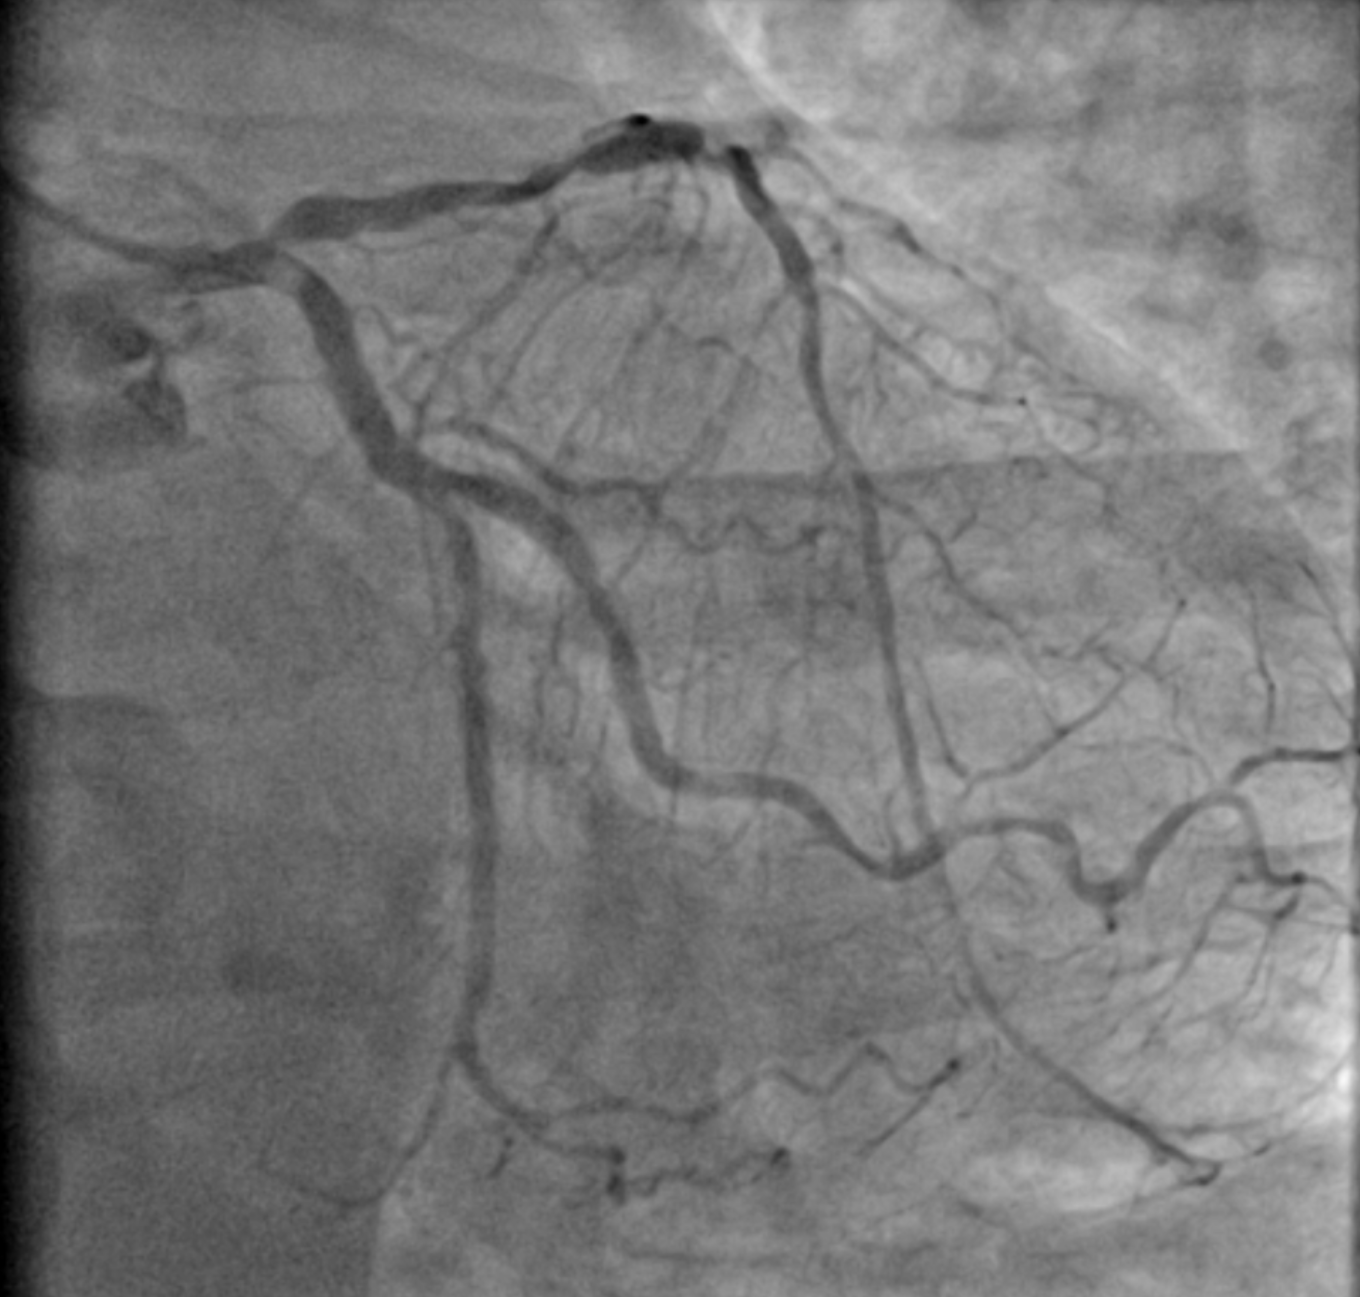

Angiography showed triple vessel disease involving LM-LAD-LCx bifurcation with eccentric calcium nodule in the ostial LCx. Severe calcification was noted throughout the proximal to mid LAD with some focal severe stenosis. RCA showed one area of severe focal stenosis.

1 rao cau .mp4